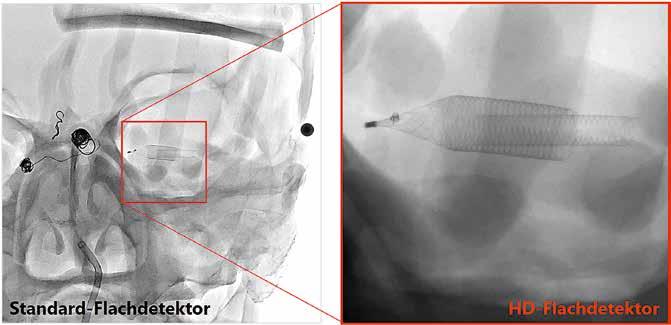

Diese neuartige Technologie ist das Ergebnis jahrelanger Forschungsarbeit, die wir in Zusammenarbeit mit führenden Kliniken, wie dem Gates Vascular Institute in Buffalo, geleistet haben. Es ist uns gelungen, den weltweit ersten hochauflösenden Flachdetektor für die dynamische Bildgebung in der Angiographie zur Marktreife zu führen. Die Auflösung des HD-Flachdetektors konnten wir auf außergewöhnliche

6,5 Linienpaare pro Millimeter steigern –

auf einen ca. doppelt so hohen Wert, verglichen mit konventionellen Systemen. Um jetzt auf Ihre Frage zurückzukommen, können damit kleinste Gefäße und Gefäßanomalien mit

kleinsten interventionellen Devices sicherer und schneller behandelt werden, was diese Technologie insbesondere für die Behandlung zerebraler Gefäßerkrankungen prädestiniert.

Standard-Flachdetektor

HD-Flachdetektor

Durch die Vergrößerungsmöglichkeit im HD-Modus können diese kleinen

Devices und Gefäßstrukturen auf dem Monitor klar dargestellt werden. Somit ist auch der Behandlungsfortschritt genauer nachvollziehbar. Der HDFlachdetektor funktioniert in diesem Zusammenhang wie ein Mikroskop für den Neuroradiologen. Es leuchtet ein, dass die HD-Technologie daher zu besseren Behandlungsergebnissen und höheren Überlebensraten führt.

Bildgebung mit Standard- und HD-Flachdetektor.

Was können Sie zur Qualität des vergrößerten Bildes sagen?

Die Bildqualität ist herausragend. Die Pixeldichte unseres HD-Flachdetektors ist so hoch, dass ein Detektorsichtfeld (englisch: field of view) der Größe von 8 cm x 8 cm auf einem 19-Zoll-Monitor bildschirmfüllend in nativer Auflösung dargestellt wird. Ohne an Bildqualität zu verlieren, sind native Vergrößerungen bis zu einem Detektorsichtfeld von 4 cm x 4 cm möglich. Im Vergleich dazu können Standard-Angiographiesysteme nur bis zu einem Detektorsichtfeld von ca. 8 cm x 8 cm nativ vergrößern. Das auf dem oben genannten Monitor angezeigte native Bild hätte dann nur eine Größe von einem Viertel der Displayfläche. Für die bildschirmfüllende Darstellung müssten die angezeigten Detektorpixel auf die doppelte Größe „aufgebläht“ werden, was natürlich mit einem Verlust an Bildqualität einhergehen würde.